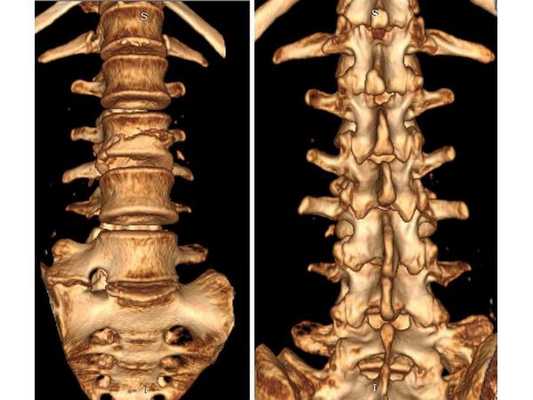

КТ пояснично-крестцового отдела позвоночника показала состояние после перенесённого спондилодисцита L2-L3 (воспалительного заболевания инфекционного характера) с разрушением тела L3 позвонка и кифотической деформацией (искривлением позвоночника) на данном уровне.

Состояние после перенесённого спондилодисцита L2, L3 позвонков с формированием абсолютного стеноза (критического сужения просвета в позвоночном столбе) на уровне L2-L3 и развитием нижнего парапареза

После операции в неврологическом статусе наблюдается положительная динамика: умеренный парапарез в нижних конечностях почти полностью регрессировал, жалобы на "онемения в ногах" также исчезли. На контрольной КТ видно состояние после успешной декомпрессии на уровне L2-L3 и установки транспедикулярной фиксирующей системы на уровне L1-L4.